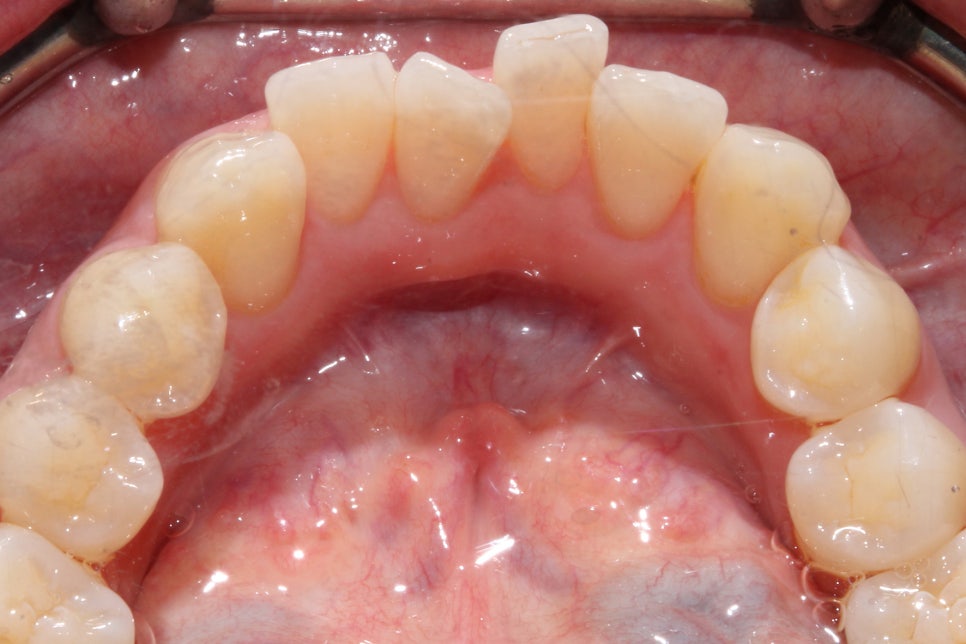

신논현역치과 교정 후 상하악의 교합면을 보시면

상악 중절치의 뻐드러짐 증상이 확연하게

사라진 것을 확인할 수 있는데요,

하악의 경우 교정 전 전치부의

삐뚤거림이 심했던 모습에서 교정 후

안모의 형태가 U자에 가까운 모습으로

교정된 것을 확인할 수 있습니다.